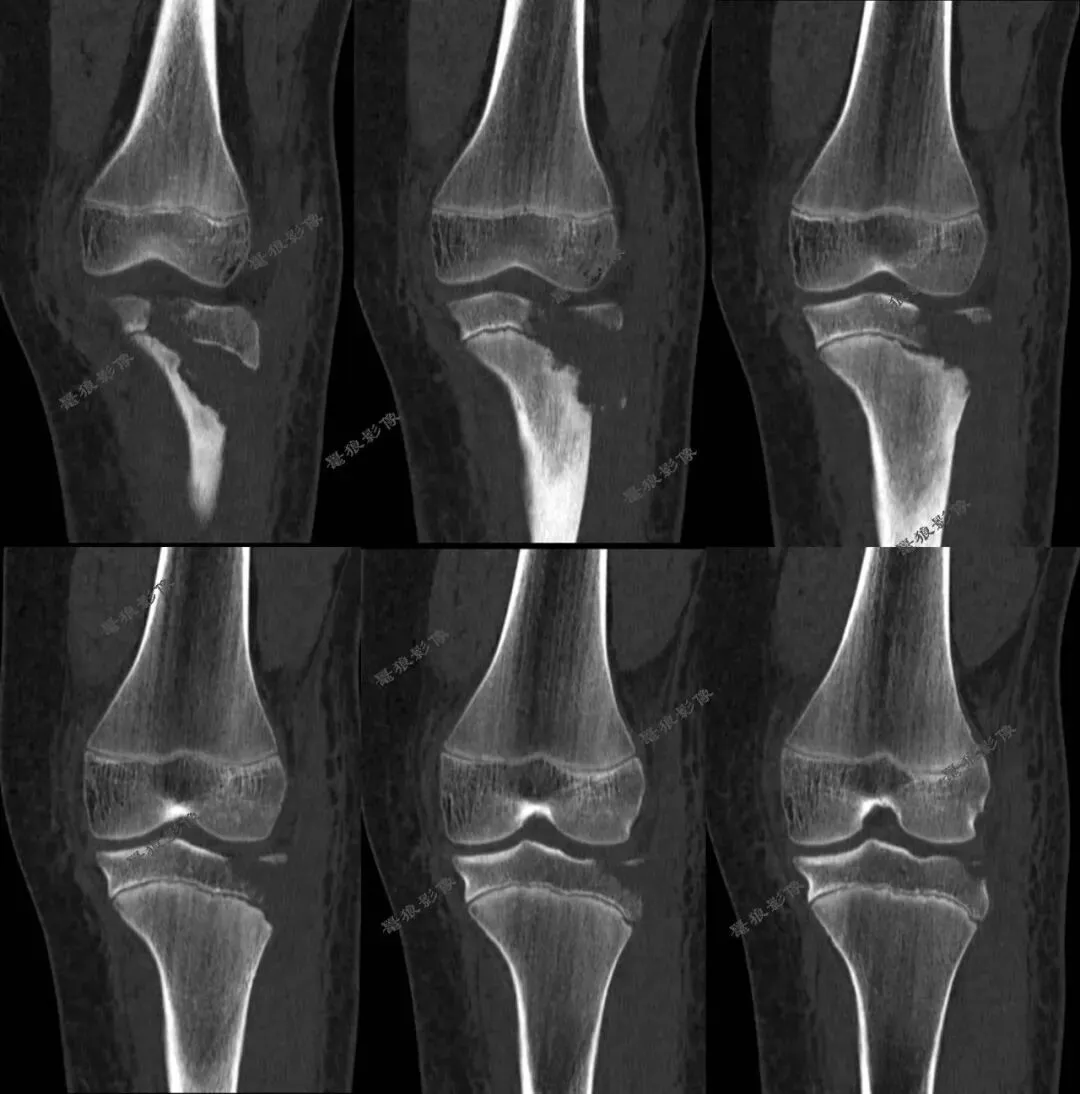

二.术前CT

胫骨结节骨折(OgdenIIIA型 )

一.任一提示 Ogden II型 及以上的骨折,应高度警惕骨折累及关节内延伸与后方干骺端成分,推荐CT进行三维重建和软组织评估,必要时联合MR检查。

二.胫骨结节骨折以骨折线走行、骺板及关节面受累情况,以及骨折移位、粉碎程度为核心,直接关联是否需要手术、术式复杂度和并发症风险。